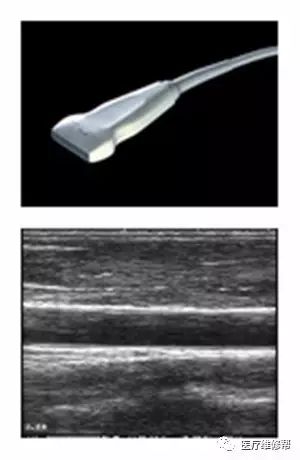

(二)一般常见的B超探头

1、凸阵探头3.5MHz 2、线阵探头3.5MHz 3、高频线阵7.5MHz 4、腔体探头6.5MHz 5、心脏探头3.2MHz 6、相控阵探头3.0MHz 7、三维探头3.5MHz